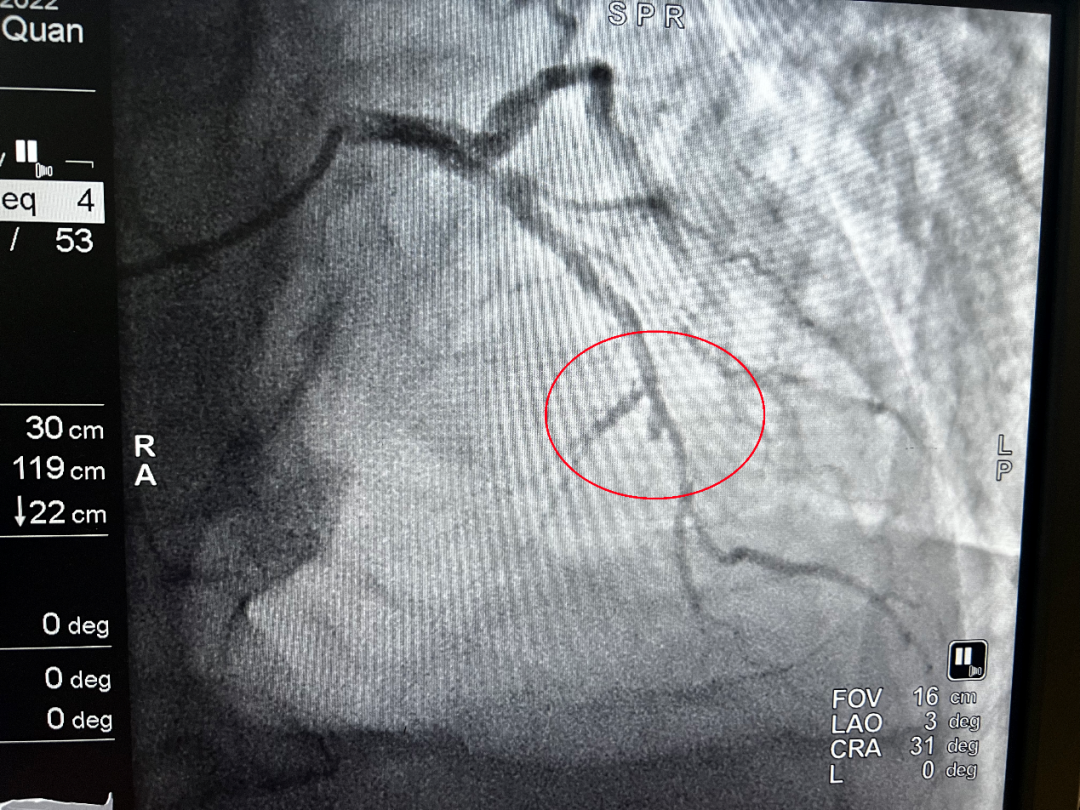

王大爷的胸痛症状持续不缓解,完善心电图后提示急性ST段抬高型心肌梗死。“时间就是心肌、时间就是生命。”我院胸痛中心立即为王大爷启动胸痛救治绿色通道,虽然患者核酸结果未出,但心血管内科医护人员在做好防护的前提下,仍然为患者开展了紧急介入手术。

(介入前)

(介入后)

凌晨1点34分,导管室激活;1点38分,患者平车送入导管室;1点48分,穿刺成功;2点01分,导丝通过血管闭塞处……从王大爷首次医疗接触到导丝通过,仅用时54分钟。所有医护人员绷紧神经,争分夺秒,为患者开辟了一条脱离危险的绿色通道。术后,患者胸痛症状明显缓解,转危为安。